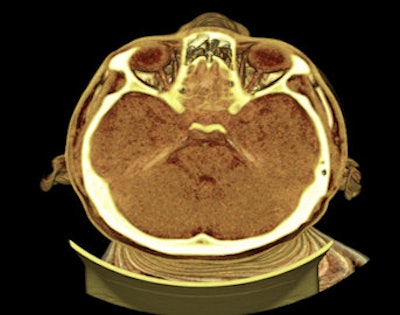

The first unit is due to open later in October, and will be located in an extension to Sheffield's Medico-Legal Center, at which the city council mortuary and coroner's services are already based. The CT slices will range from 0.625 mm to 0.5 mm, as higher spatial resolution is required. A whole-body scan of 170 cm in length, for example, will generate around 3,400 slices that will be transferred to a high-performance computing server and undergo 3D rendering of DICOM and grayscale multiplanar images at a 3D workstation. Specific protocols will enable visualization of the body's outer layers that contain hair and skin.

"It is just as important for forensic pathologists to visualize the outer layers as the internal layers as this is where bruises and abrasions can be found. In criminal cases, this might be the entry and exit wounds of bullets, knives, or in the case of alleged suicide, where the small cuts over the wrist leading to extensive hemorrhaging would cause death," explained iGene's Chief Operations Officer and Lead Forensic Pathologist Dr. Pramod Bagali.

Visualization of the vertebral column, which is not straightforward in a classical autopsy because dissection of the spine is time-consuming and involves the sawing of the spinous process of vertebral bodies.

The scanning module, iDASS (Digital Autopsy Software Systems), lies at the heart of the process, enabling pathologists to visualize and analyze a complete 3D image of a body in near real-time. In expected and nonsuspicious deaths in the elderly, for example, the system will allow proper documentation of a death, even if imaging is not required, while at the other end of the scale, the system can cater for a full criminal investigation forensic autopsy, complete with 3D panoramic views of the crime scene, according to Chandran.